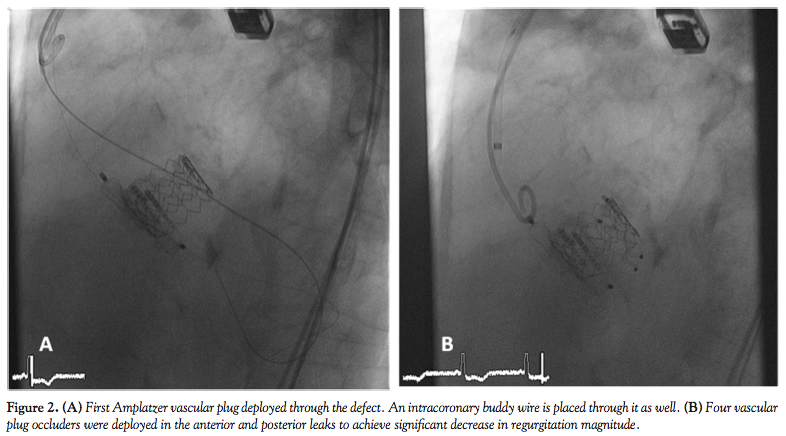

In this situation, we therefore scheduled the patient to make an attempt to close the paravalvular leak by percutaneous route using vascular plug occluders, under general anesthesia and with transesophageal echo (TEE) guidance. Using an 8 Fr right femoral approach, a straight-tip Terumo 0.035˝ guidewire was placed first through the anterior leak and a 5 Fr Terumo Vertebral Glidecath (Terumo Europe) was passed to the LV. The Terumo wire was retrieved and exchanged by an Amplatz Extra Stiff guidewire (Cook Medical). Through this guidewire, an AGA Amplatzer TorqVue 45° 8 Fr sheath (AGA Medical Corporation) was placed in the LV through the defect. Subsequently, the Amplatz wire was retrieved and a 14 x 5 mm Vascular Plug III (AGA Medical Corporation) was deployed (Figure 2A). Due to residual shunt, another Vascular Plug III (10 x 5 mm) was placed in the same defect after

re-crossing the defect, with a significant decrease in insufficiency magnitude. The delivery cable of the first device was not released until the second device was placed through the defect to avoid the possibility of dislodgment. During the positioning and deployment of the occluders, a 0.014˝ intracoronary buddy-wire was kept in the defect to maintain the position if further intervention was requested. The same maneuvers were carried out with the posterior leak, and again two Vascular Plug III occluders of the same dimension were placed through the defect (Figure 2B). A control angiogram showed that, after treatment, the global degree of angiographic regurgitation was now mild and with a significant decrease from the initial angio (Figure 3A). An excellent result was also ascertained from the TEE monitoring (Figure 3B).